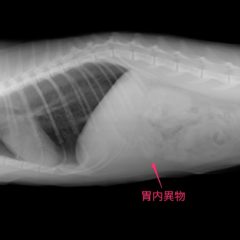

解答 解説 ある物 を誤飲したとして来院した80歳代女性 実践 画像

解答 解説 ある物 を誤飲したとして来院した80歳代女性 実践 画像

解答 解説 ある物 を誤飲したとして来院した80歳代女性 実践 画像

解答 解説 ある物 を誤飲したとして来院した80歳代女性 実践 画像

薬のptp包装の誤飲 高橋ペットクリニック 福岡県春日市の犬猫動物病院

犬や猫の吐き気が収まらない 身近な物を食べてしまっている 誤飲

薬のptp包装の誤飲 高橋ペットクリニック 福岡県春日市の犬猫動物病院

犬や猫の吐き気が収まらない 身近な物を食べてしまっている 誤飲

犬の誤飲によるptpシートを内視鏡で摘出除去 石川台どうぶつ病院

薬のptp包装の誤飲 高橋ペットクリニック 福岡県春日市の犬猫動物病院